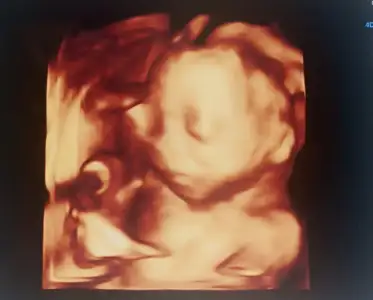

- 29 Kasım 2023

- 2.005

- 2.546

- 63

- 29

Benim ilk gebelik yaptıracağım gibi ben valla. Bu arada gerçekten günler hiç geçmiyor. Çalışmasak herhalde saat sayardıkGünler gecseydı sankı hıc gecmıyor sonra şeker testı zamanı zaten şeker yaptırmayı düşünmüyorum hıc oğlan da sekerım cıkmamıstı hıc